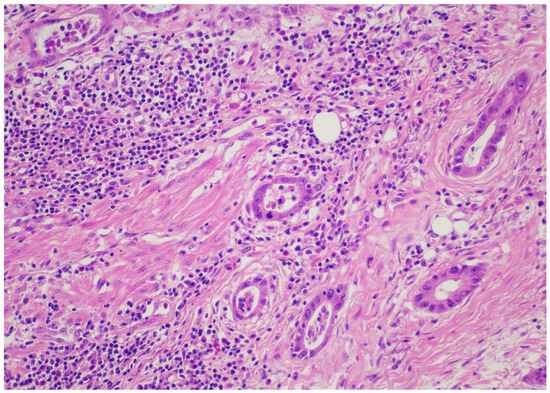

Records from patients with gastric or esophageal adenocarcinoma operated on in a single academic institution during the time period from January 2022 until January 2024 were reviewed after institutional review board permission. Demographics, including age and gender, were recorded for all patients. Only patients with adenocarcinomas who underwent esophagectomy or gastrectomy according to respective tumor location were included. Only patients who were operated on after the completion of the neoadjuvant FLOT regimen were included in the analysis. Type of operation performed and pathology reports/relevant pathology slides were reviewed, including total number of lymph nodes, positivity or negativity of lymph nodes, node positivity after regression, and node negativity with regression. Tumor regression (TRG) score was reported according to the Mandard classification [21]. TRG values ranged from 1–5, with 1 designating no residual cancer cells, TRG 2 residual cancer cells, TRG 3 fibrosis outgrowing residual cancer, TRG 4 residual cancer outgrowing fibrosis, and TRG 5 absence of regressive features. Staging was performed according to the American Joint Commission on Cancer (AJCC), 8th edition [22]. All relevant slides were also reviewed to calculate TIL scores for all patients, expressed as a numerical score, according to relevant guidelines from international consortia on tumor-infiltrating lymphocytes [23]. When no tumor could be identified after neoadjuvant treatment, by definition, no TIL scores could be assigned. More specifically, a review of the pathology slides measurement of TILs did not require any stains on the slides but rather only calculating TIL scores from “measuring” the number of lymphocytes relevant to the tumor. The reader is directed to the aforementioned reference for the exact protocol used to calculate TIL scores. Pathology reports for all relevant operations were reviewed, and pathology slides were re-reviewed by 2 independent expert pathologists (CG and DR) to calculate the TIL score. A TIL score from 0–80 was granted, and where no tumor was found, “no tumor” was designated for TIL score calculations. Figure 1 and Figure 2 depict slides from our patient cohort, with the first corresponding to a TIL-high patient, while the latter originates from a TIL-low patient.

The SPSS package [IBM SPSS statistics version 29.0.2.0(20)] was used for all statistical analyses. In order to create subgroups of TIL patients of sufficient sample size, we created two groups for TILs, namely TIL-low and TIL-high groups, with the TIL-low group containing scores from 0–30 and the TIL-high group containing numbers from 40–80. Representative pictures from pathologic slides from our patient series are provided in pictures 1 (TIL-low) and 2 (TIL-high). We affirmed that both TIL-low and TIL-high groups contained more than 25 patients each, and therefore, by definition, we assumed that the sample size followed a normal distribution and included categorical data; thus, Spearman’s r correlative statistic could be used for analysis. With regards to the Mandard score, we stratified patients into a “good response” TRG1 and TRG2 and a “bad response” TRG 3, TRG 4, and TRG 5. Correlation analysis between TRG and the TIL-low or TIL-high group was performed using the Spearman’s r statistic and Kendall’s tau statistics.

Figure 1. TIL-high patient.